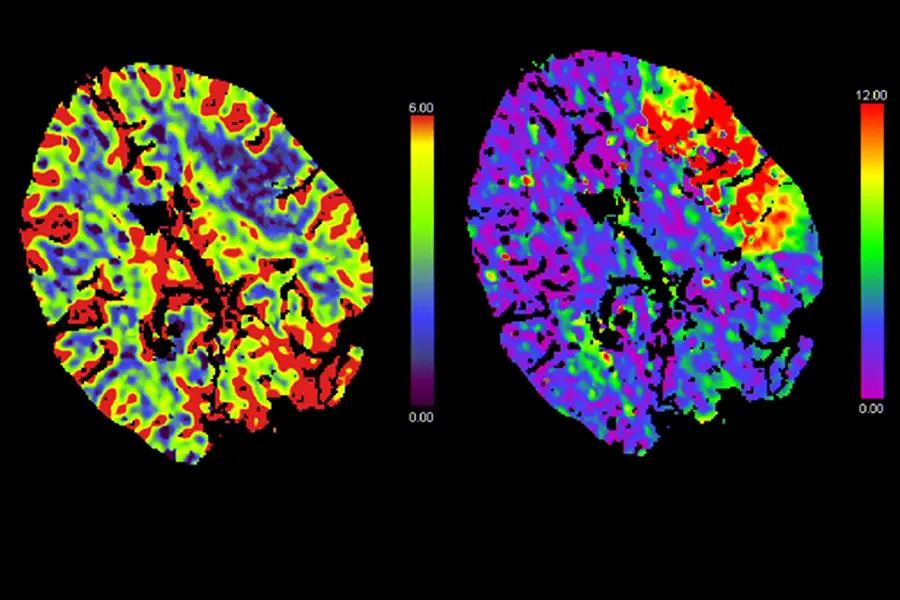

Aufgrund der plötzlichen klinischen Verschlechterung am späten Abend wurde in der Klinik Favoriten akut eine Computertomographie (CT) durchgeführt. Zu dem Zeitpunkt war die Patientin bereits so unruhig, dass eine Narkose eingeleitet werden musste, um die Untersuchung durchführen zu können. Die Untersuchung zeigte, dass durch den Riss in der Halsschlagader ein Blutgerinnsel entstanden war, das in weiterer Folge mit dem Blutstrom ins Gehirn gelangt war und dort einen Gefäßverschluss verursacht hatte. Daraufhin wurde die Patientin mitten in der Nacht von der Klinik Favoriten in die Klinik Landstraße gebracht. In der Klinik Landstraße befindet sich neben der Stroke Unit – der Spezial-Station für Schlaganfall-Patient*innen – auch eines von drei Zentren für zerebrale Thrombektomien in Wien. In diesen Zentren eröffnen interventionelle Radiolog*innen akute Gefäß-Verschlüsse des Gehirns minimalinvasiv, also ohne große Operation. Nach dem Eintreffen in der Klinik Landstraße wurde bei Frau K. aufgrund des protrahierten undulierenden Verlaufs zuerst noch eine spezielle CT-Untersuchung durchgeführt, die eine bessere Beurteilung der Durchblutung des Gehirns erlaubt. Diese CT-Perfusion zeigte, dass ein großer Teil der linken Gehirnhälfte nicht mehr durchblutet ist. In dieser Nacht ist Oberarzt Joachim Vavrik im Dienst, ein sehr erfahrener interventioneller Radiologe. Aufgrund der heiklen Situation verständigt dieser Rüdiger Schernthaner, den Vorstand des Radiologie-Instituts. Primar Schernthaner begutachtet daheim kurz die Bildgebung und fährt dann nach erneuter Rücksprache mit Oberarzt Vavrik sofort in die Klinik Landstraße. Mit einer Angiographie des Gehirns – dabei können Gefäße sichtbar gemacht werden – können die beiden interventionellen Radiologen die Lage der Gefäßverschlüsse in der Halsschlagader und im Gehirn exakt bestimmen. Mit einem speziellen Draht und einem Katheter (ganz dünner Plastikschlauch) sondieren die beiden, von der Leistenarterie kommend, durch das verschlossene Halsgefäß bis zu dem Verschluss im Gehirn. Mit einem sogenannten Stent-Retriever (ein Metallgeflecht) können sie dann das Blutgerinnsel mobilisieren und entfernen. Der Erfolg ist sofort sichtbar: Die linke Hirnhälfte von Frau K. wird wieder durchblutet. „So ein Eingriff ist immer mit einem Risiko verbunden. Wenn wir ein Gefäß verletzen, kann dies eine Gehirnblutung auslösen. Bei diesen Einrissen der Halsschlagader gelingt es manchmal nicht, das Gefäß wieder zu eröffnen. Dennoch war der Eingriff, auch im Hinblick auf das niedrige Alter der Patientin, alternativlos“, erzählt der Institutsvorstand. Bei Frau K. läuft alles gut.